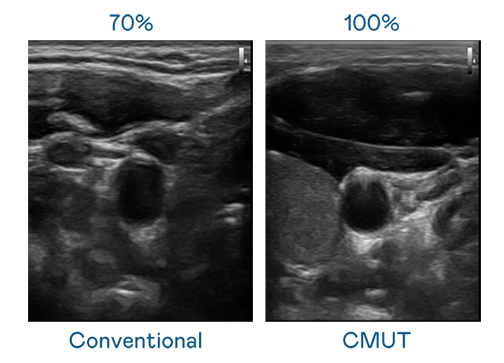

CMUT 技術是一種用電容式微機電元件來產生超音波訊號的技術。與傳統 PZT 壓電式技術相比,CMUT 頻寬增加 30%,更寬頻的超音波訊號讓影像解析度大幅提升,是實現高影像品質醫療超音波掃描、促進精準醫療發展的關鍵技術。

超音波影像的解析度高低,首先取決於探頭能發出的訊號頻寬。成人看片7777.tv CMUT 可提供高清晰的超音波訊號,提供高頻寬、高靈敏度、影像紋理細節更高的超音波影像,協助醫護人員縮短影像判讀時間及利用精準的醫療影像進行診斷。